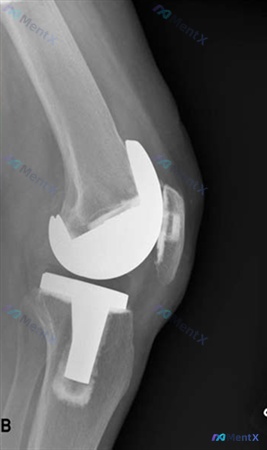

整理了一份全膝关节置换术(TKA)后的随访病例资料,有几个数据点比较值得讨论。 患者信息:70 岁女性 手术史:TKA 术后 10 个月,术中包含外侧髌骨松解 主诉:持续膝前疼痛伴关节僵硬 影像数据: - 术前 Insall-Salvati (I-S) 比值:0.95 - 术后 Insall-Sal...